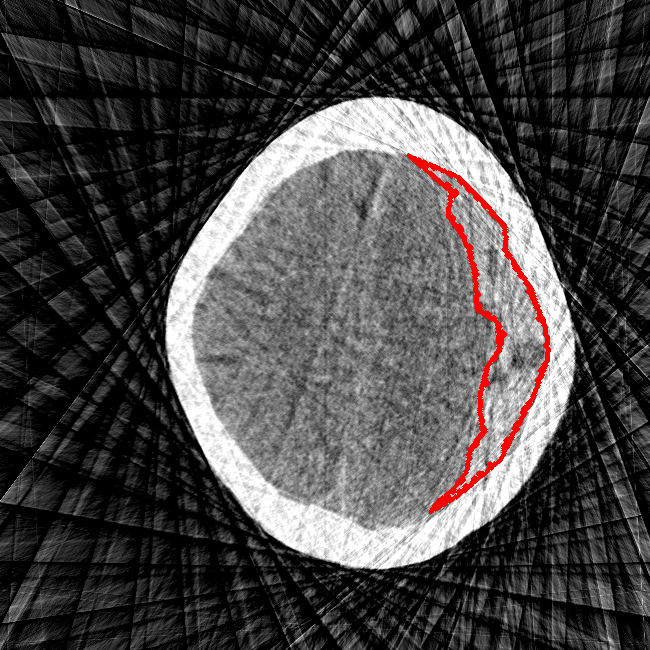

Limited Angle

CT GMAIMMbench Disease Diagnosis

Limited Angle - L0 (Original)

L0

L0 (Original)

Question

This is a CT image. Which of the following options is the most appropriate to demonstrate the marked area?

A brain hemorrhage B barrett's esophagus C thyroid nodule D retinal hard exudates

Ground Truth: A. brain hemorrhage